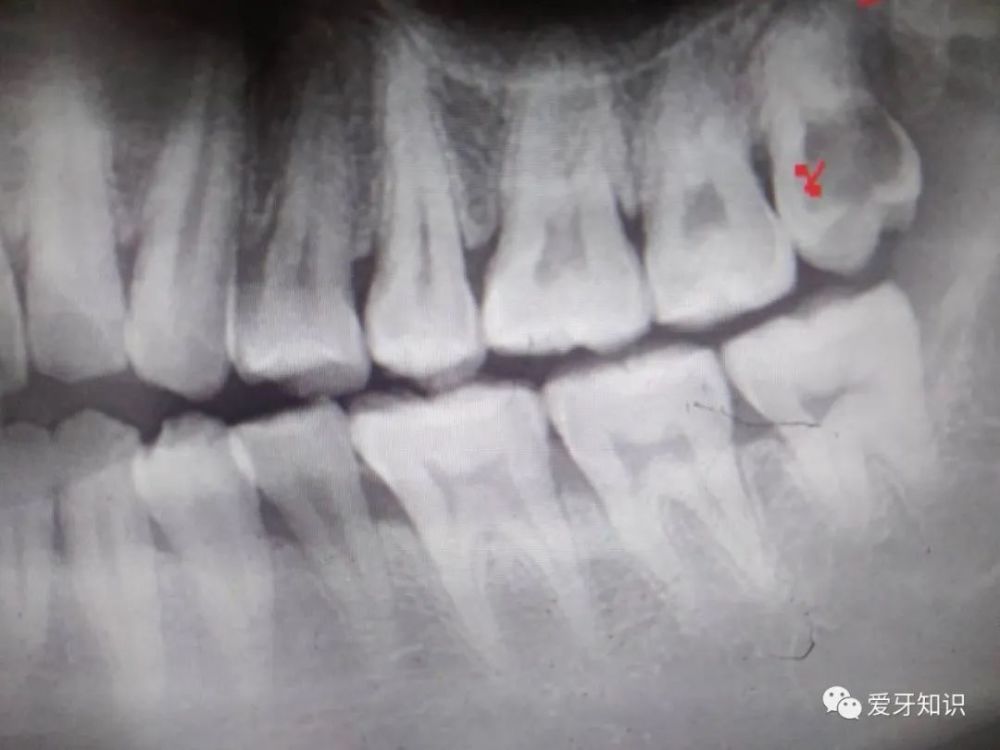

智齒周圍食物阻塞 不易清潔 造成大臼齒後方深部蛀牙 利用樹脂全瓷嵌體修復 牙科美容資訊 美容牙科張凱榮醫師